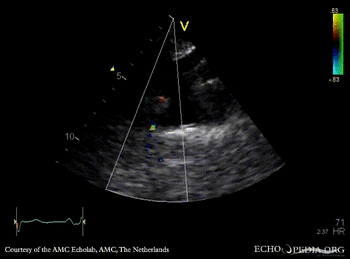

Coarctatio aortae

Suprasternal view Suprasternal view: Collor Doppler, high velocity flow in descending aorta